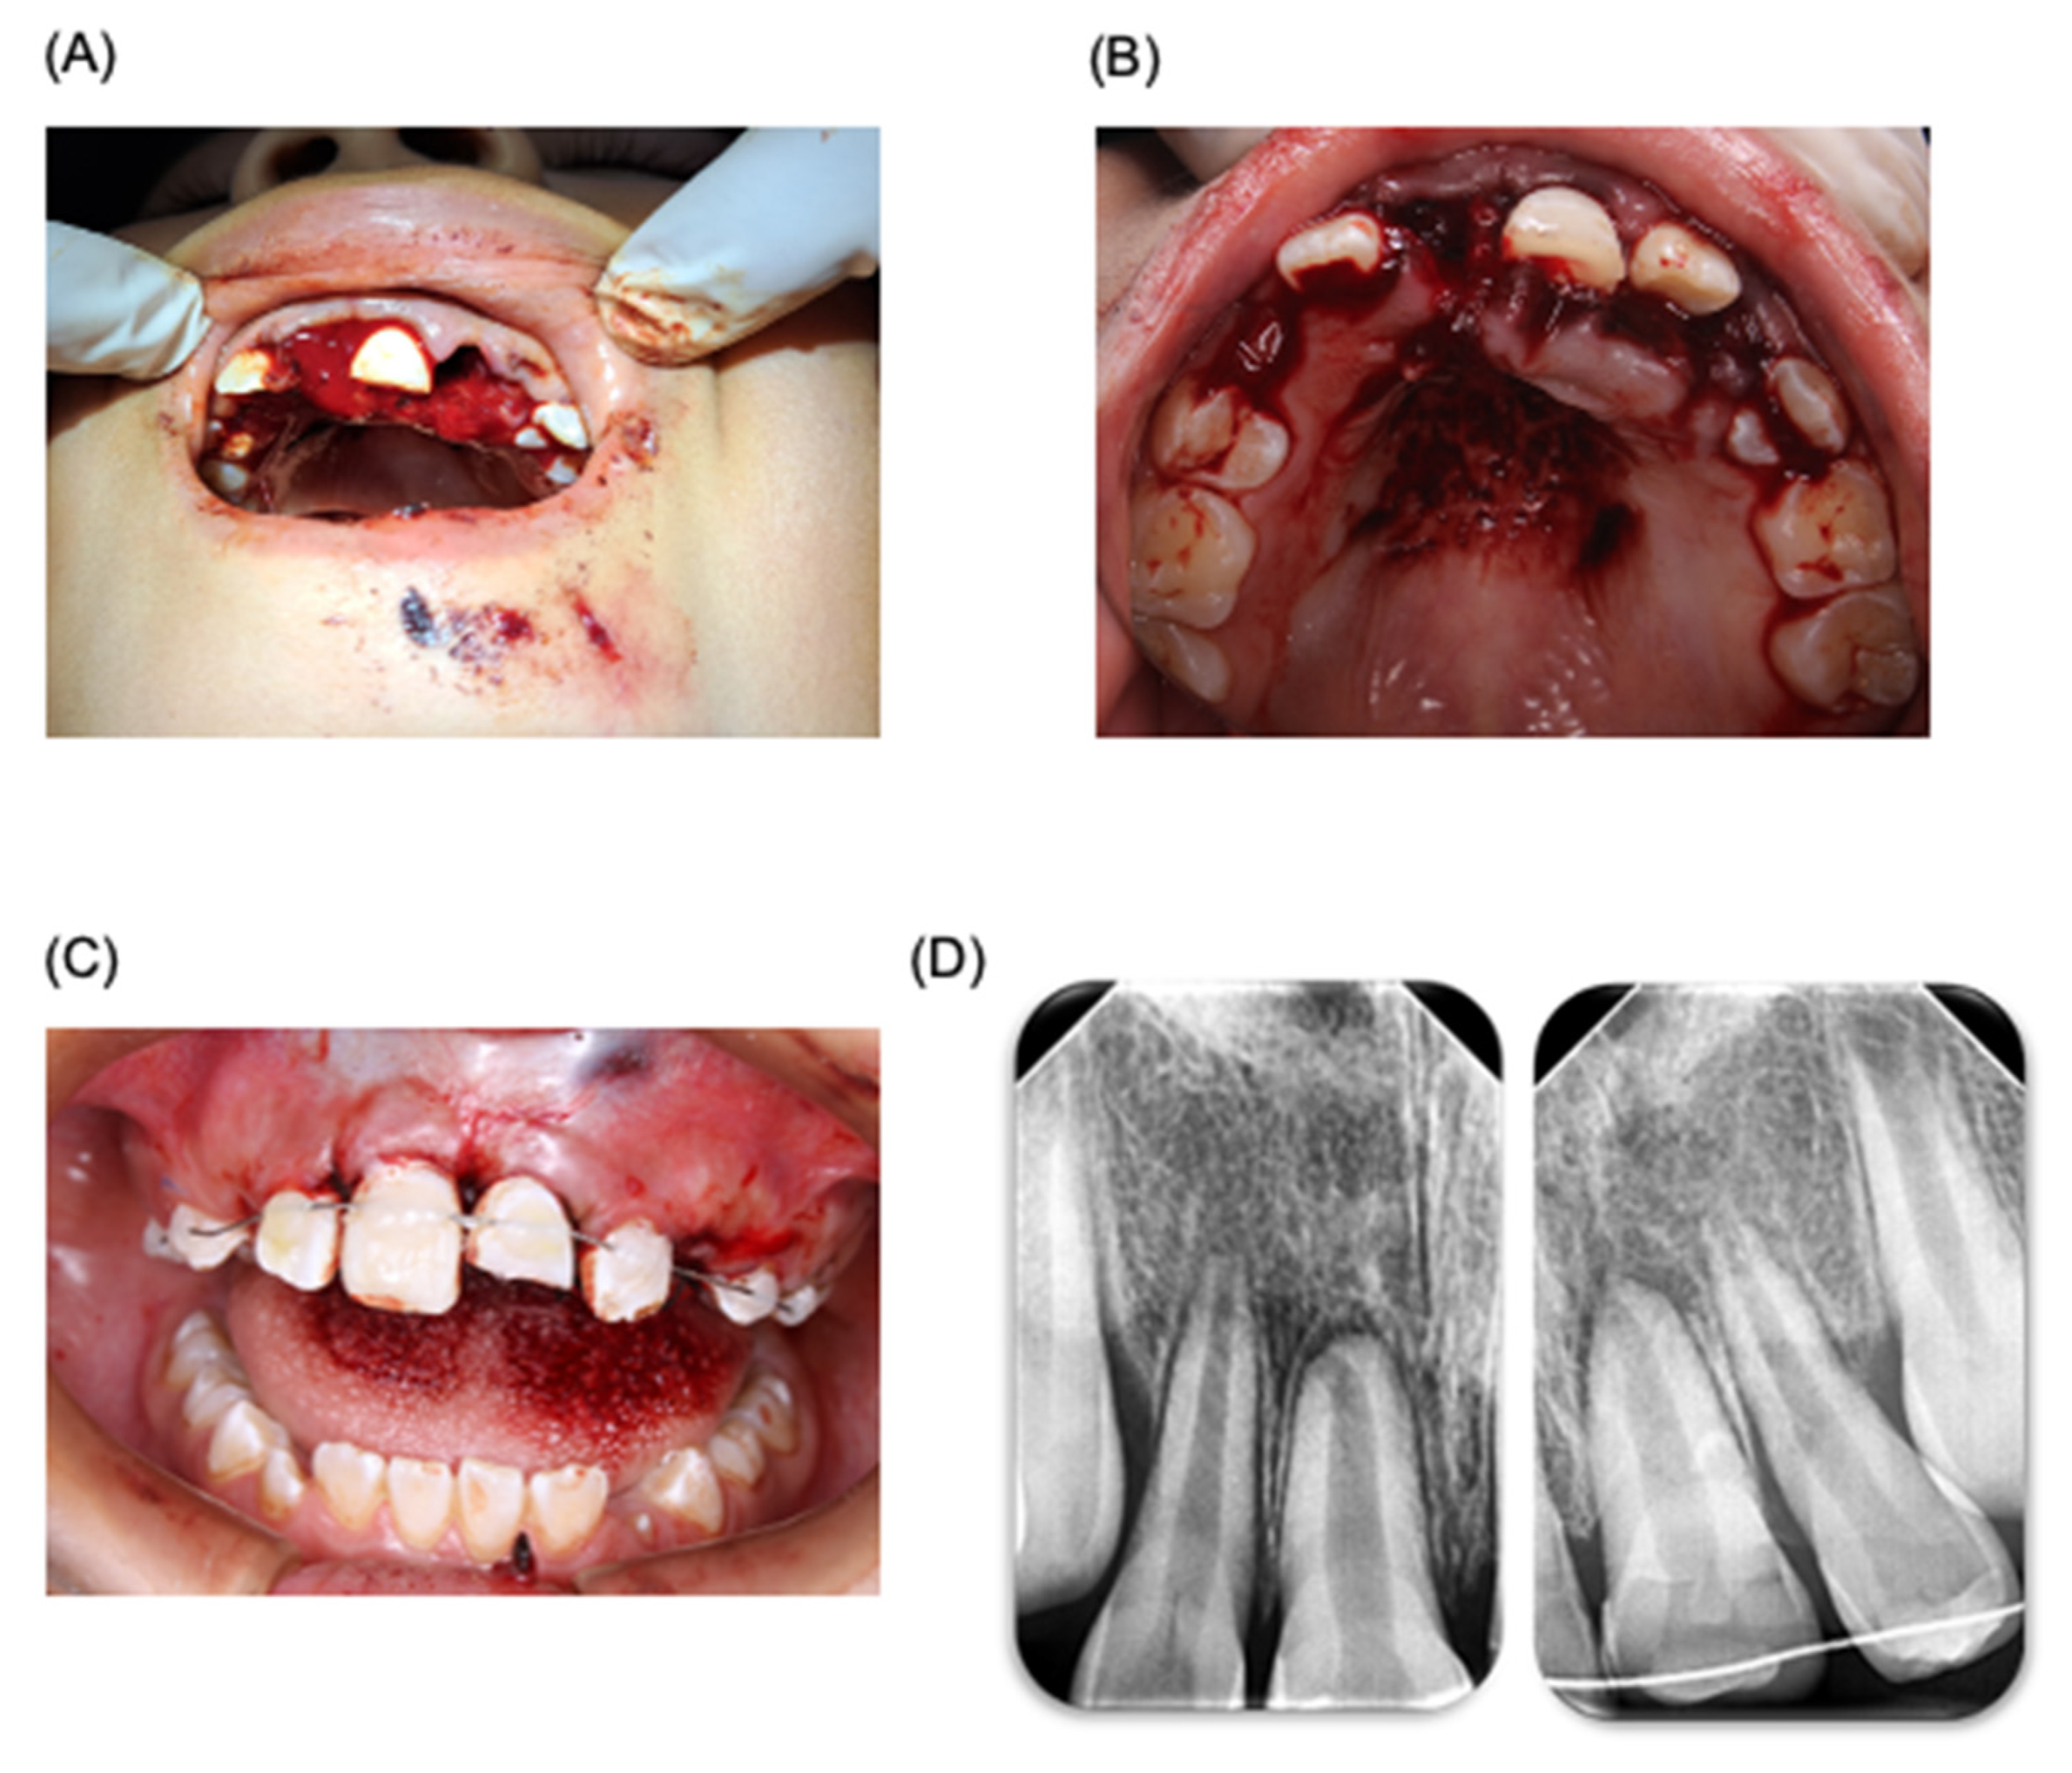

For the treatment plan, digital periapical radiographs (radiovisograph, Woodpecker Medical Instrument Co., i-sensor H2, Guilin, Guangxi, China) were taken of the trauma area. The area was carefully rinsed with saline solution (PiSA, Guadalajara, Jalisco, Mexico), and anesthesia (articaine 4%, ZEYCO, Zapopan, Jalisco, Mexico) was administered using an infiltrative technique. Curettage of the socket was performed for the reimplantation of tooth 22, applying gentle digital pressure. A digital periapical radiograph was taken to confirm the placement. The same procedure was applied to the other avulsed tooth 11 (Figure 1). It is worth mentioning that the avulsed teeth were rinsed with saline solution before reimplantation. Tooth 21, which had suffered extrusive luxation, was washed with saline solution. A passive splint was made using 0.014 braided wire, extending to teeth 65 and 55 (ten teeth in total, from molars to upper molars). The splinting procedure involved cleaning the area, applying etching acid (3M, St Paul, MN, USA), drying, applying adhesive (3M, MN, USA), and photocuring for 20 s. The splint was placed passively, and fluid composite resin (3M, MN, USA) was used. Periapical radiographs were taken, and the area was sutured with 4-0 silk (ETHICON, Raritan, NJ, USA) using simple stitches (Figure 1). Post-treatment, the patient was prescribed the following medications: amoxicillin/clavulanic acid (400/57 mg/5 mL, every 12 h, for 7 days), acetaminophen (500 mg, every 8 h, for 3 days), ibuprofen (400 mg, every 8 h, for 3 days), and chlorhexidine 0.12% (Lacer, Barcelona, Spain) for 7 days. The patient was told to consume a soft diet for at least 3 weeks. In addition, the case was reviewed by an oral and maxillofacial surgeon regarding the proposed treatment plan (Department of Oral and Maxillofacial Surgery, Faculty of Dentistry, Autonomous University of San Luis Potosi, SLP, Mexico).

Figure 1.

Odontology treatment of patient. Management of dentoalveolar trauma in pediatric patient. (A) Photograph of dentoalveolar trauma in pediatric patient. (B) Reimplantation of tooth 22. (C) Management of trauma using a wire–resin splinting technique. (D) Periapical X-ray after splinting treatment.